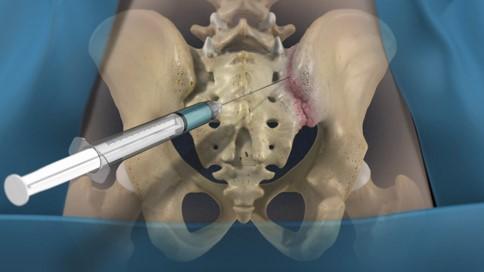

• Infiltrações na Articulação Sacroilíaca (intra-articulares):

• Injeções de corticosteroides (anti-inflamatório potente) combinados com anestésicos locais diretamente na articulação sacroilíaca. Guiadas por fluoroscopia (raio-X em tempo real) ou ultrassom para garantir precisão, podem proporcionar alívio significativo da dor por um período.

• Dor crônica (> 3 meses)

• Diagnóstico clínico, com ou sem exame de imagem comprobatório

• Injeção de anestésico e corticosteróide local (normalmente uma aplicação é suficiente)

• Feita sob anestesia (sedação + local). O paciente não sente dor.

• Alta no mesmo dia

• Resultados máximos após 30 dias.